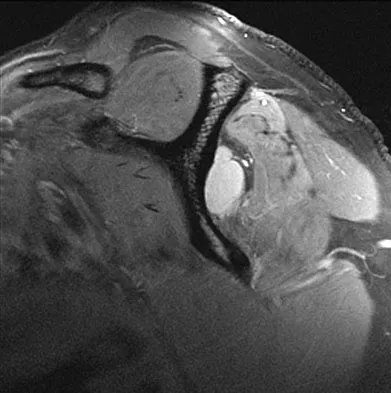

A 62-year-old man with a long history of right shoulder pain and weakness is scheduled to undergo hemiarthroplasty. Based on the radiographs shown in Figures 6a through 6c, what preoperative factor will most affect postoperative functional outcome?

Explanation

The radiographs reveal osteoarthritis and proximal humeral head migration. Integrity of the rotator cuff must be questioned based on these radiographic changes. The status of the rotator cuff is the most influential factor affecting postoperative function in shoulder hemiarthroplasty. The coracoacromial ligament provides a barrier to humeral head proximal migration in the face of a rotator cuff tear. The radiographs do not indicate significant humeral head or glenoid erosion. Acromioclavicular arthritis is often asymptomatic. Iannotti JP, Norris TR: Influence of preoperative factors on outcome of shoulder arthroplasty for glenohumeral osteoarthritis. J Bone Joint Surg Am 2003;85:251-258.